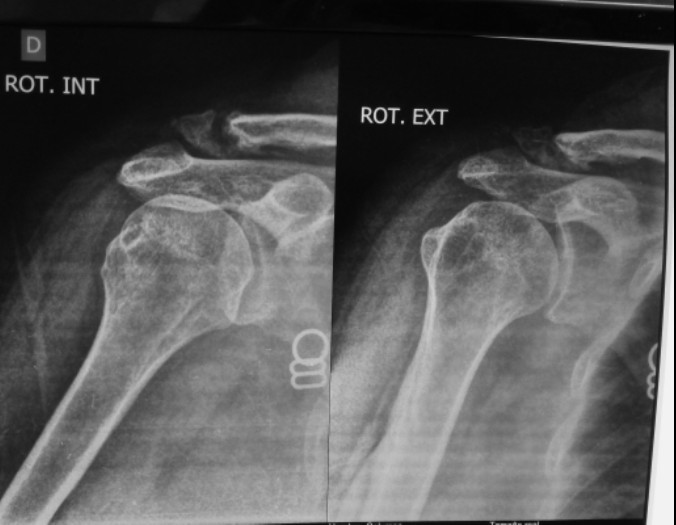

|  Отправлено Dr Konstantin  19 Январь 2021, 00:05  Частная медицина за рубежом Господа коллеги, нужны ваши мнения. Имеется пациент женщина, возраст 45 лет. Перелом более двух лет назад. Год назад ей сделали операцию по удалению осколка. Остается боль, усиливающаяся в при некоторых движениях. Желает оперироваться.

Поскольку есть дефект, то надо либо укорачивать ключицу, либо костную пластику делать. Я думаю аутопластику из крыла подвздошной кости делать.По фиксации- 2 варианта. Крючковидная пластина или же по Веберу.Крючковидная пластина- плюс в том, что можно оставить навсегда. Минусы- сложно будет "насадить" мелкий отломок и имплантант на винты.В общем, какие мнения? Что еще можно использовать? Какие перспективы вообще для сращения?

| По рентгенограмм. Пытались сделать проекции по Занку, оценивается максимальное расстояние между ключицей и клювовидным отростком, судя по снимкам оно увеличено, вывод - повреждение треугольной связки, подвывих в ключично-акромиальном суставе. Значит, только удаление отломков дистального конца не даст ожидаемый результат. Подумайте о Weaver-Dann.